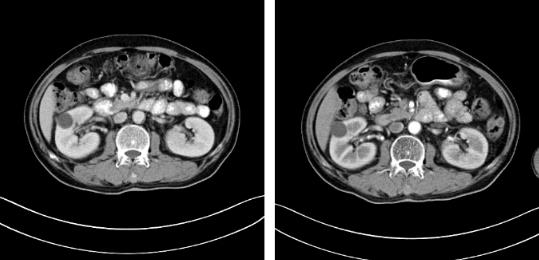

2017年9月29日,從CT影像看到右腎情況更為嚴重。為減緩腫瘤增長的速度,專家進行商議后,最終決定由牛立志教授主刀為安圖叔叔進行了右腎腫瘤冷凍消融術。手術開始后,牛立志教授在CT和超聲引導下,同時使用兩根冷凍針固定病灶,精準滅活腫瘤;術后很成功無不良反應。術后一周進行第二次雙腎腫瘤冷凍消融術。安圖叔叔兒子笑道:“當時真的很緊張,醫生勸慰我無須擔心,都交給他們,我們都很清楚知道父親的病情,真的很感謝也很慶幸我父親遇到復大的醫護人員,免受開刀之痛。住院期間醫護人員很盡心盡力的照顧父親,手術的成功離不開他們的辛勞付出。”

隨著時間的推移,安圖叔叔身體開始發生明顯變化,腰疼的癥狀得到緩解,血尿的次數明顯減少,睡眠質量有明顯的改善。以前上廁所都是一件很痛苦事情,如今逐漸正常。安圖叔叔的病情得到改善,在一次次的復查中得到主治醫生王峰的佐證。過去的兩年里,安圖叔叔一直遵循醫生的囑咐,按時服藥定時回院復查,到目前為止是安圖叔叔第9次來院復查。安圖叔叔的兒子說道:“我每次帶父親來檢查都有新發現,腫瘤在一天天的變小,我們很相信醫生的話,他們會給我們最好的治療方案,如今已過去兩年,父親身體和精神慢慢轉好,這是我們所希望的。”